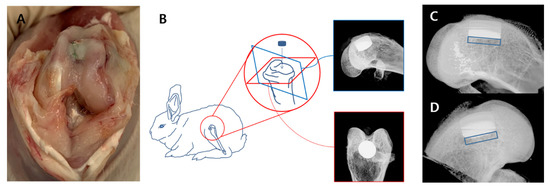

2.4.1. Surgical Procedure

2.4.3. X-ray

3.5. In Vivo X-ray